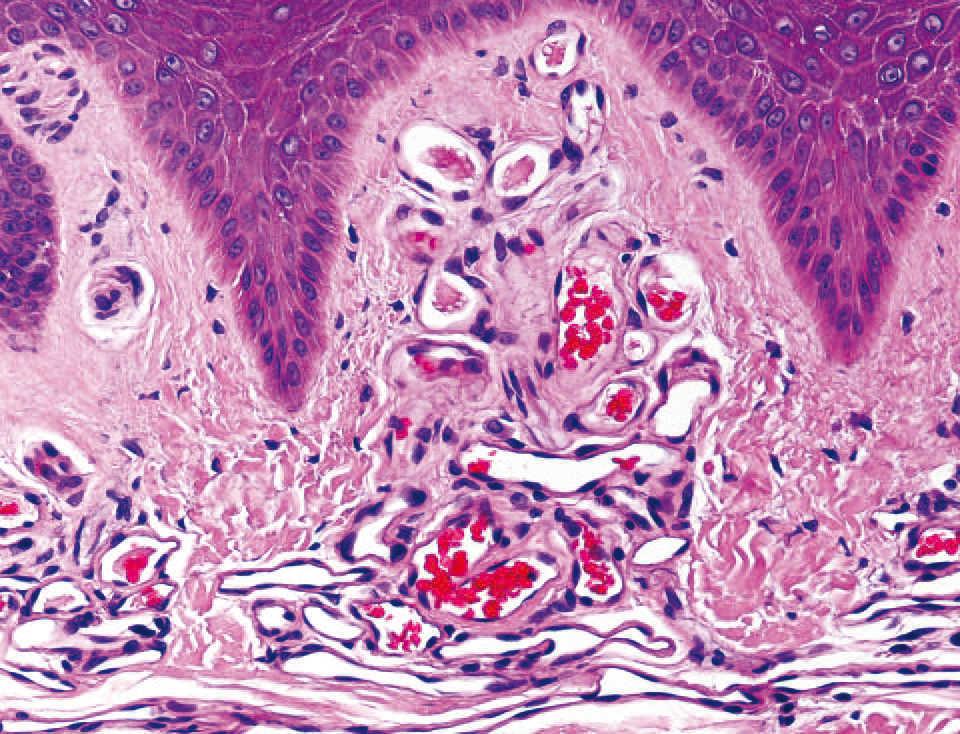

Realizamos una biopsia de la lesión y en el estudio histopatológico destacaba, bajo una epidermis conservada, una proliferación de vasos capilares agrupados en ovillos, con estroma laxo, localizados en las papilas dérmicas (figs. 2 y 3). En el resto de la dermis no existía infiltrado linfocitario ni ningún otro hallazgo patológico. La inmunotinción con CD 31 resultó positiva para las células endoteliales (figs. 4 y 5).

Figura 3. Detalle de la proliferación de vasos capilares agrupados en ovillos, con estroma laxo. Hematoxilina-eosina, 60.